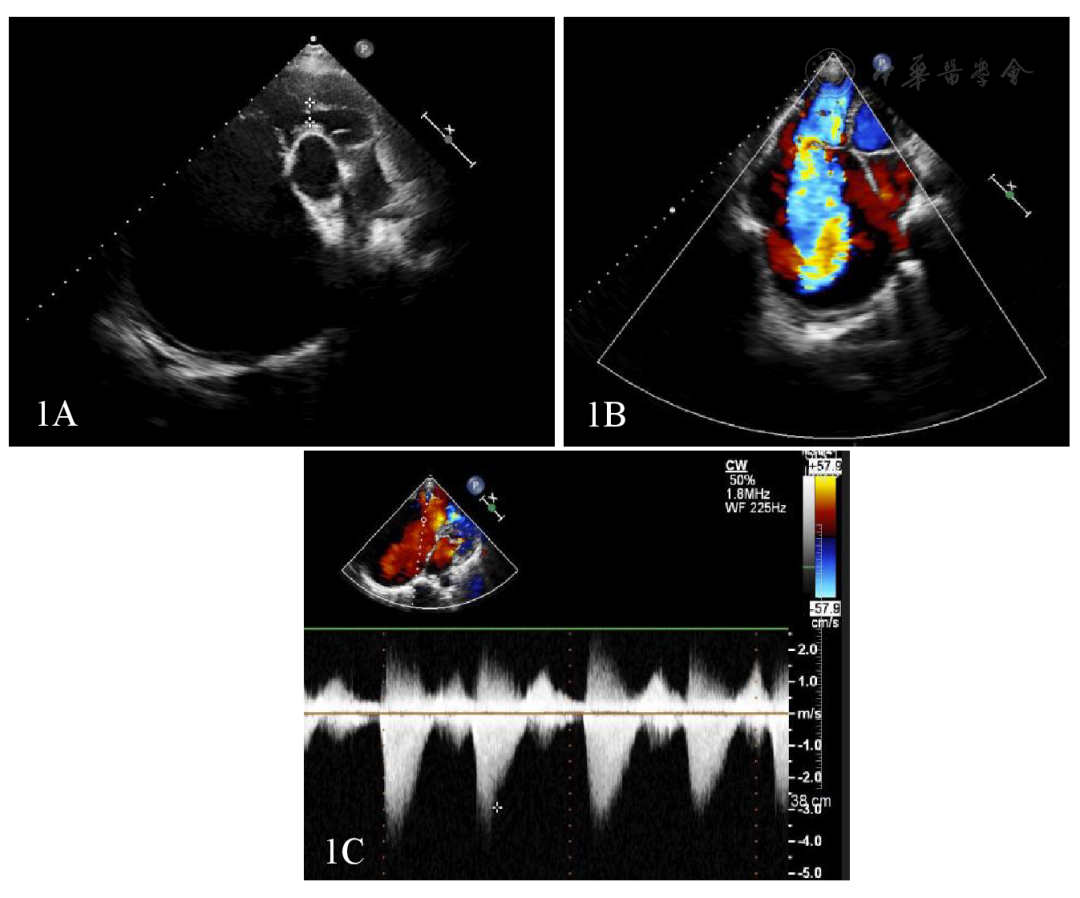

随着显示器上逐渐显现出一个跳动的影子,王教授一边调整着不同视角,一边向记录员简要描述着当下的情况:「心脏往左下移位,心腔明显扩大变形。」

没等我回复,王教授继续扫着:「心尖四腔心切面,右房室增大。右房上下径约 12.6cm×10.2cm,三尖瓣极重度反流……」

「胸骨旁大动脉短轴切面:右室流出道前壁肌束增厚,舒张期右室流出道最窄处内径,约 1.2cm……剑突下切面,右室舒张末期面积约 24.2cm^2,右室收缩末面积约 15.5cm^2,面积变化约 35.9%。」

王教授调整至彩色多普勒模式,对我说:「你看, 这里能看到,收缩期,三尖瓣有大量反流,而且右室流出道血流增速。」

「你再看!看到没有?右室流出道的前壁这段肌束增厚,其实就是把右心室一分为二了……」我把手机上的图片放大,推给坐在一旁正在吃饭的师妹看。

「所以是右室双腔心?结果一直以为是特发性肺动脉高压,这不是开国际玩笑吗!」师妹发出的疑问,就和几天前的我自己一模一样。

如今,小姨的病情终于明朗,困扰她多年的并非是特发性肺动脉高压,而是一种少见的先天性疾病:右室双腔心。

右室双腔心,也称为双腔右心室,右心室异常肌束、被分隔的右心室或三室心。

在患双腔右心室的患者中,右心室的异常肌束横跨右心室腔,止于右心室流入道部分的前壁。异常肌束的阻塞部位常发生在右心室腔内的小梁部,阻塞程度从轻度狭窄道完全阻塞,将右心室分隔为流入部的高压腔和流出部的低压腔,因此,右心室到肺动脉的血流受阻。

「理论上确实不应该出现。」王教授说,「这个患者诊断的主要难点在于,她的双腔右心室病程长,并发症也多,心肺疾病进展到心衰阶段,单从症状上来看,很难和特发性肺动脉高压区别开。」

「从我们超声的角度来看,患者的声窗透声条件不够好,右心室形状不规则、心脏明显重构变形,不容易获得标准切面,也很难了解到患者心脏全貌。」王教授说,「这个时候,就容易出现一个情况,叫『格式塔效应』。」

而这名患者在早期检查心超时,有可能是还没有出现三尖瓣极大量反流,右室壁增厚处于收缩高动力状态,因此,医生错误地认为高右心室压力代表肺动脉高压。

随着时间推移,患者右心功能失代偿,三尖瓣极重度反流,进入右室流出道的血量减少,且右室流出道与声束方向角度过大,并没有发现及监测到高速血流,此时,右室双腔心的诊断就更是难上加难了。」